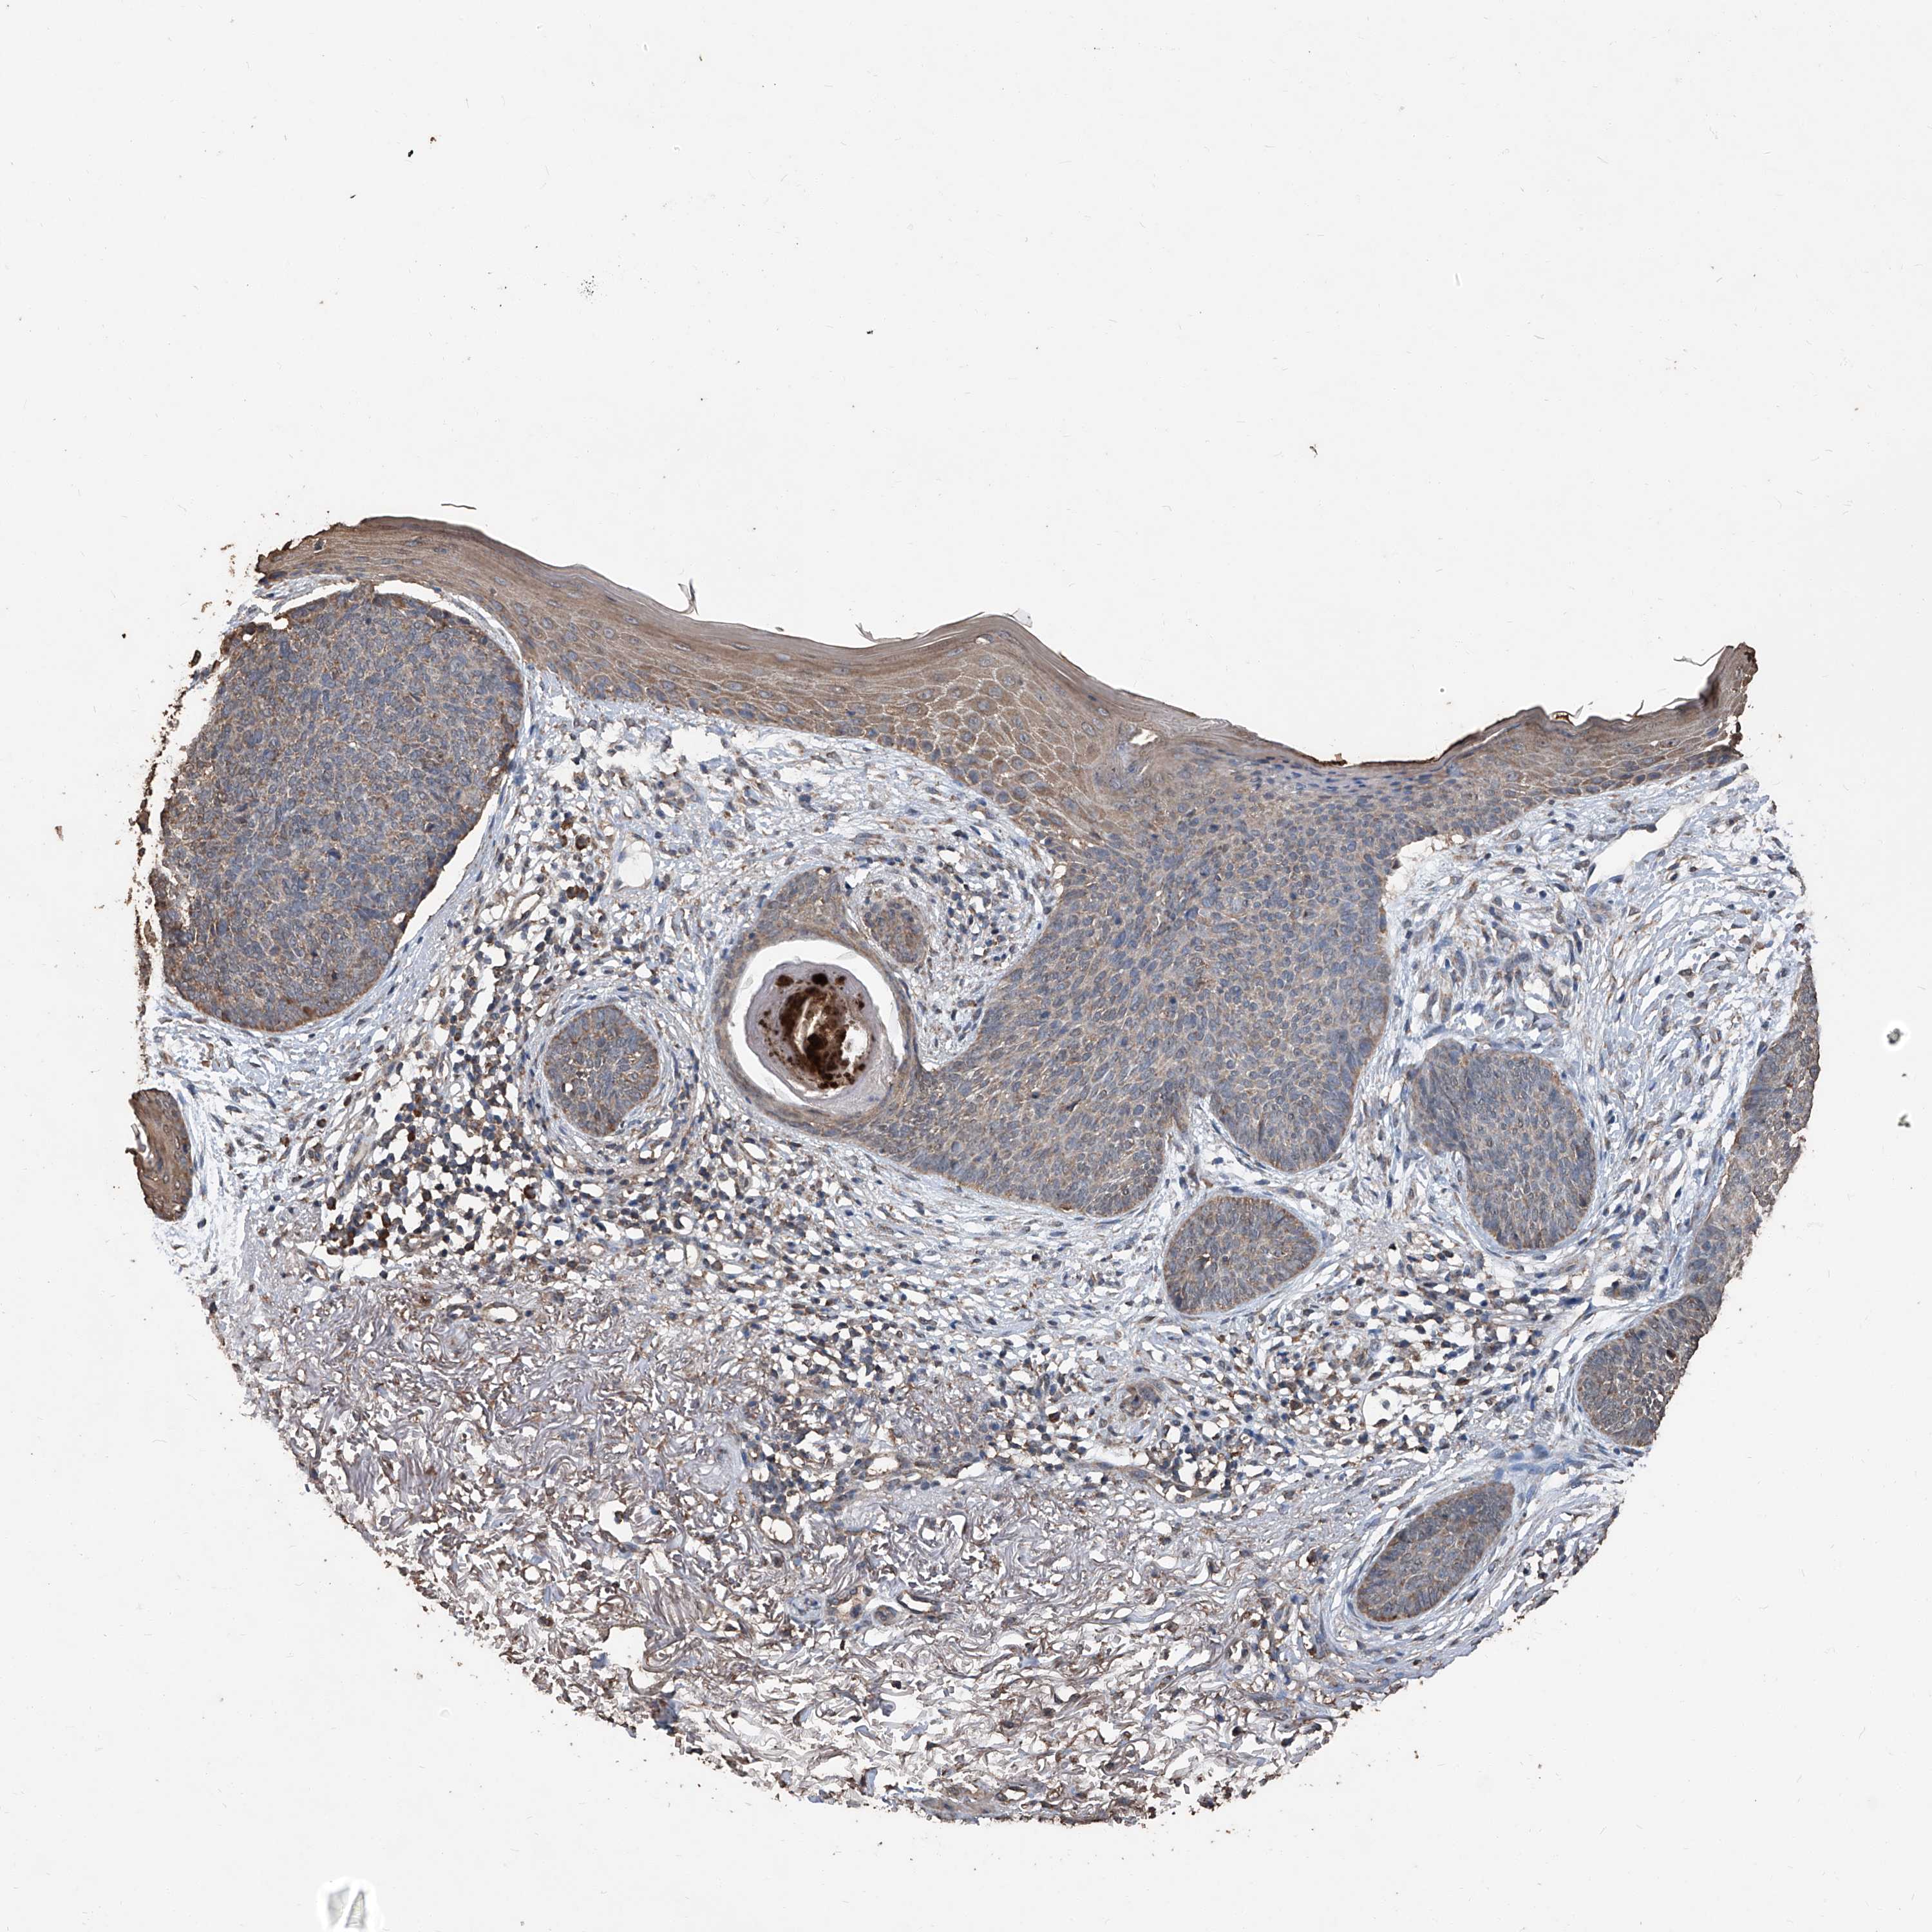

Basal cell and squamous cell cancer

SKIN CANCER - Protein expressioni

A mouse-over function shows sample information and annotation data. Click on an image to view it in a full screen mode. Samples can be filtered based on level of antibody staining by selecting one or several of the following categories: high, medium, low and not detected. The assay and annotation is described here.

Antibody stainingi

Antibody staining in the annotated cell types in the current human tissue is reported as not detected, low, medium, or high, based on conventional immunohistochemistry profiling in selected tissues. This score is based on the combination of the staining intensity and fraction of stained cells.

Each image is clickable and will lead to virtual microscopy that enables deeper exploration of all samples and also displays staining intensity scores, fraction scores and subcellular localization as well as patient and tissue information for each sample.

Antibody HPA064978

Antibody CAB033965

Staining

High

Medium

Low

Not detected

Intensity

Strong

Moderate

Weak

Negative

Quantity

>75%

75%-25%

<25%

None

Location

Nuclear

Cytoplasmic/membranous

Cytoplasmic/membranous,nuclear

Basal cell carcinoma

Squamous cell carcinoma, NOS